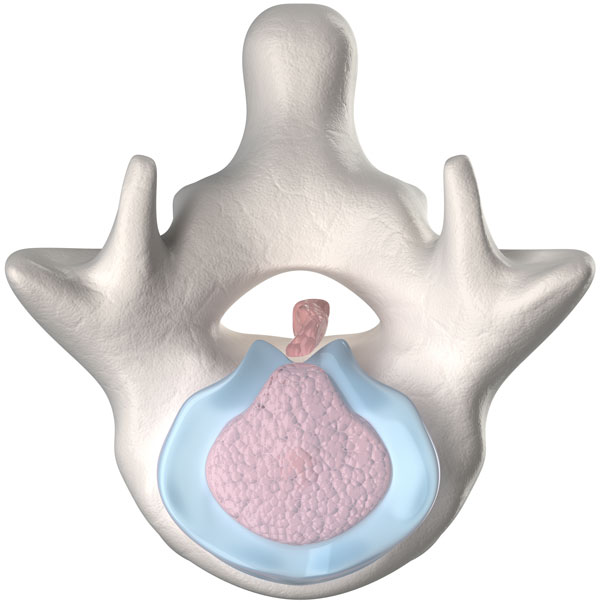

- Bulging Disc

- Canal Stenosis

- Spinal Stenosis

Platelet Treatments for Pain from Bulging or Herniated Discs

A bulging disc is also called a disc protrusion or bulge. This means that the outer covering of the disc (annulus) is partially torn or damaged and the inner gel is causing the area to bulge. This can put pressure on a spinal nerve and cause numbness and tingling (sciatica).

A herniated disc is also called a disc extrusion, slipped disc, sequestration, or “HNP” (Herniated Nucleus Pulposis). This means that the outer covering of the disc (annulus) is completely torn or damaged and the inner gel squirts out. This can put pressure on a spinal nerve or cause severe swelling and lead to numbness and tingling (sciatica).